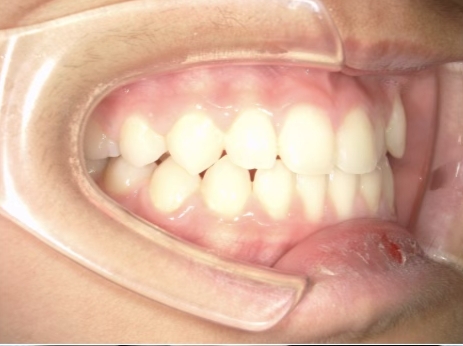

治療中④ 小4:10y1m

左上3が八重歯で萌出中